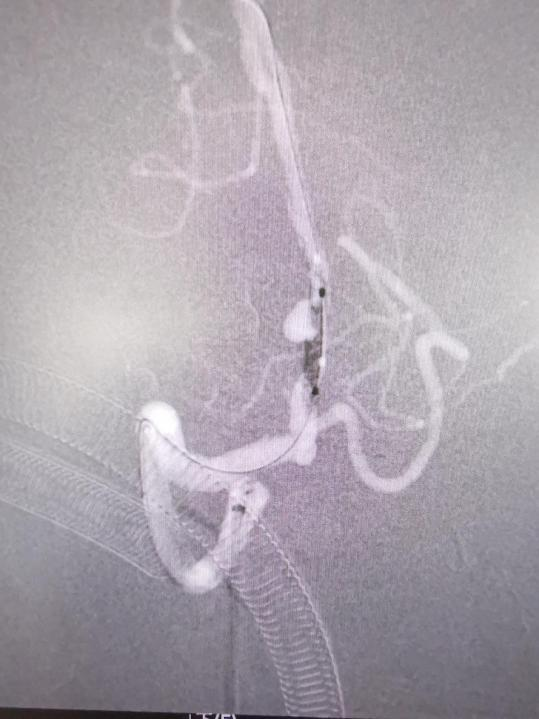

经过头部dsa检查,诊断张先生的椎动脉V4段动脉瘤为夹层动脉瘤。

神经外科团队经过深入分析和讨论,认为采用目前最先进的血管导向密网支架植入术是最佳治疗方案。相较于传统手术,这种新型手术具有更高的安全性和简便性,尤其适合复杂、难治性动脉瘤的治疗。经与患者和家属充分沟通交流,同意实施手术。

经神经外科团队与手术室、放射科、介入治疗中心等多学科紧密合作及省医院程美雄专家教授的悉心指导下,手术顺利完成。

密网支架专业名称为血流导向装置,是近年神经介入医生的“新武器”,通过密网支架的高金属覆盖率和高网孔率设计,对局部血流进行重塑,将载瘤动脉向动脉瘤内的冲击血流导向远端正常血管内,从而减少局部血流对动脉瘤的冲击,使动脉瘤内的血流动力学情况得以改善,密网支架外动脉瘤内形成血栓,进而实现动脉瘤的闭塞。

血流导向密网支架置入技术是神经介入领域的新技术新疗法,改变了传统治疗理念,将以往的颅内、颈内动脉瘤血管内治疗的理念由单纯“填坑”转变成了“重新铺路”,新型的血流导向密网支架较传统的瘤体内填塞手术流程更优化、手术时间更短、安全性更好,手术疗效更令患者满意。